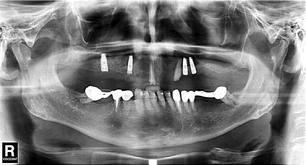

Πριν βάλετε το εμφύτευμα, γίνεται κλινικός έλεγχος και πανοραμική ή αξονική τομογραφία. Αν δεν υπάρχει επαρκές οστό, δεν μπορεί να γίνει η επέμβαση. Ο γιατρός θα πάρει το ιατρικό ιστορικό σας, καθώς άνθρωποι με σοβαρές παθήσεις, π.χ. προχωρημένη οστεοπόρωση ή αρρύθμιστο διαβήτη, δεν μπορούν να βάλουν εμφυτεύματα. Επίσης, για να τοποθετηθούν εμφυτεύματα σε παιδιά, θα πρέπει να έχει ολοκληρωθεί η ανάπτυξή τους (μετά την ηλικία των 18 χρόνων).

Τα εμφυτεύματα τοποθετούνται με τοπική αναισθησία, και με τη βοήθεια ειδικών ακτινογραφιών και μηχανημάτων εξασφαλίζεται ότι θα μπουν στη σωστή θέση. Μετά την επέμβαση, τα εμφυτεύματα συνήθως καλύπτονται από τα ούλα και παραμένουν στη γνάθο 2-6 μήνες για να ενσωματωθούν με το οστό. Στο διάστημα αυτό, οι ασθενείς χρησιμοποιούν προσωρινές γέφυρες ή οδοντοστοιχίες, για να μπορούν να μασούν και να μιλούν χωρίς πρόβλημα. Κατόπιν, αρχίζει η κατασκευή και η τοποθέτηση του πορσελάνινου δοντιού πάνω στο εμφύτευμα.